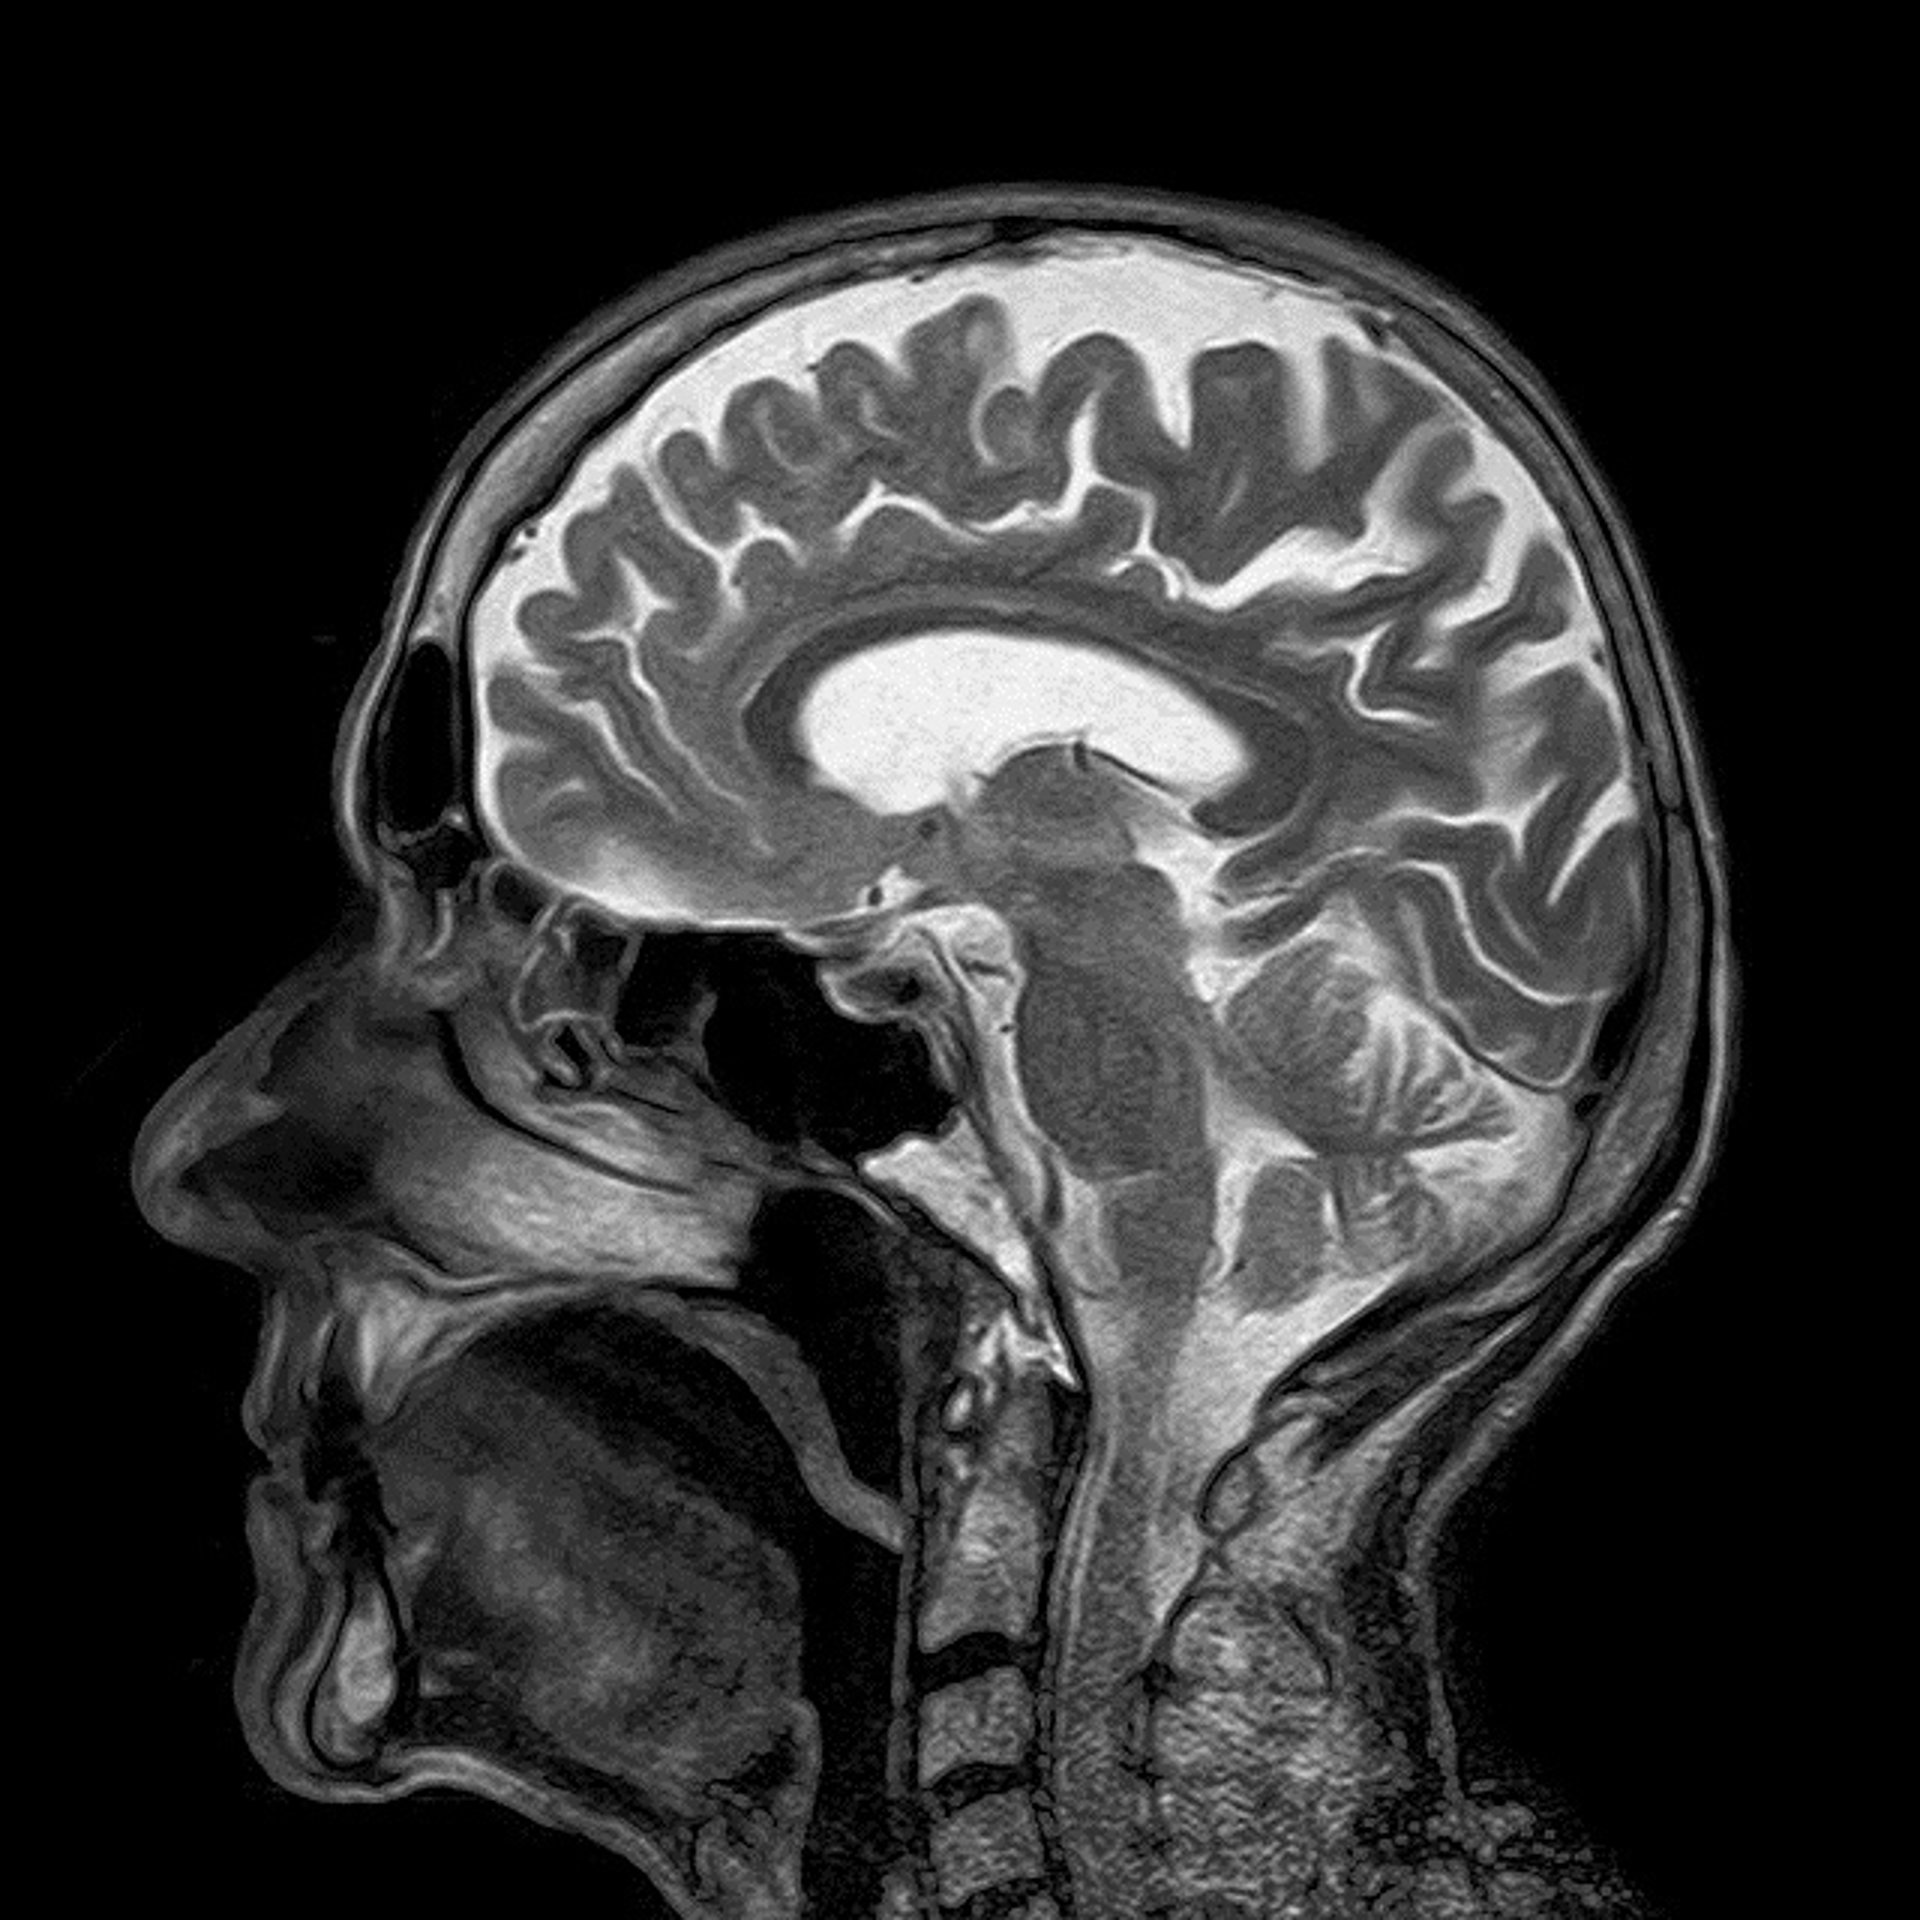

Desarrollar una herramienta que diferencia tejido sano y tumoral en una cirugía cerebral

CEREBRO

Empresas e instituciones europeas, entre ellas el Grupo Álava Ingenieros, están participando en el desarrollo del proyecto 'HELICoID' que tiene como objetivo desarrollar un demostrador capaz de discriminar entre tejido sano y tumoral en tiempo real durante una intervención quirúrgica cerebral en personas.

"Se trata de una sofisticada herramienta que aporta al neurocirujano información precisa de la localización del tumor en la sala de operaciones mediante imágenes hiperespectrales. Dado que el cáncer implica un cambio en la fisiología celular, esta alteración puede ser detectada como un cambio en la firma hiperespectral del tejido", ha explicado el miembro de la División de Diseño de Sistema Integrados (DSI) del Instituto Universitario de Microelectrónica Aplicada (IUMA) de la Universidad de Las Palmas de Gran Canaria (ULPGC) e impulsor de 'HELICoID', Gustavo Marrero Callicó.

En concreto, prosigue, esta herramienta permite visualizar con gran nitidez la frontera entre tumor y tejido sano -algo realmente complejo- en tiempo real. Las imágenes hiperespectrales que se captan del cerebro del paciente, además, van cambiando según se van extrayendo las células tumorales, por lo que los desplazamientos en la masa encefálica ya no dificultan el trabajo.